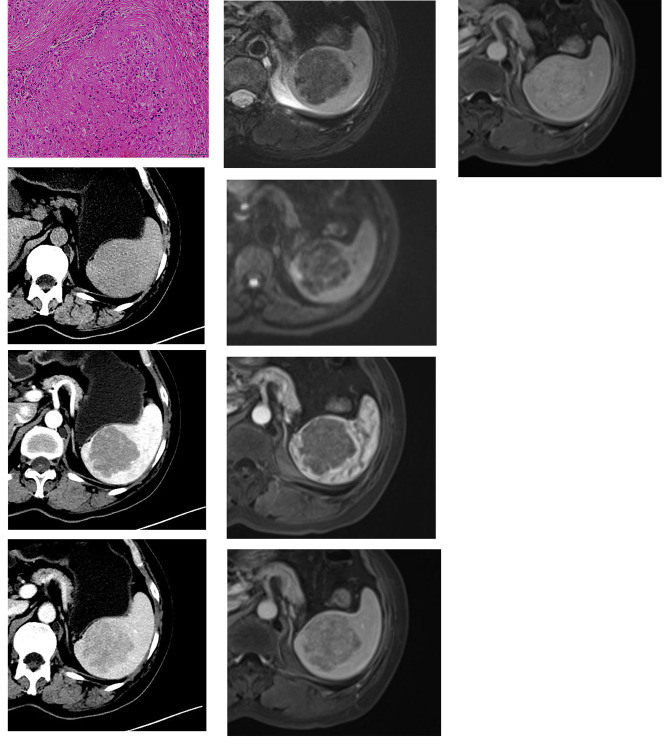

Fig. 1.

An elderly woman with a history of anemia. Microscopically, the splenic lesion consisted of variably sized nodules surrounded by variable fibrous bands (H&E, original magnification×200). There was proliferation of both collagen fiber (B) and multiple micro-vessels, with inflammatory cell infiltration(1 A). Unenhanced axial CT image (1B) shows a hypodense lesion in spleen. The lesion shows heterogeneous enhancement on arterial phase(1 C) and portal phase(1D). T2-weighted images(1E) and DWI(1 F) show a hypointensity lesion with more hypointense scars in the center. After contrast administration, the lesion shows less contrast-enhanced than the spleen parenchyma in arterial phase(1G) and portal venous phase(1 H). The lesion shows continued progressive enhancement on delayed phase(1I)

On CT, all 5 lesions showed hypodensity on non-contrast images (Figs. 1B and 2A) and progressive radial heterogeneous enhancement after contrast administration (Figs. 1C and D and 2B and C). Intralesional calcification was not seen in all 5 lesions.

The signal intensity was generally heterogeneous on both non-contrast and contrast images. Among 12 cases, 10 cases(83.3%)showed hypointensity on T2weighted imaging (Figs. 1E and 2D), and 2 cases (16.7%) showed hyperintentisy with central hypointensity. On T1 weighted imaging, 10 cases (83.3%) were isointense and 2 cases (16.7%) were slightly hypointense. One case dropped signal intensity on in- phase on T1 weighted imaging. 10 cases (83.3%) showed hypointensity on Diffusion weighted imaging (Figs. 1F and 2E) and 2 cases (16.7%) showed slightly hyperintensity on DWI. On the ADC map, only one case (8.3%) showed hypointensity, other 11 cases (91.7%) showed hyperintensity or isointensity. After contrast administration, all 12 lesions showed progressive enhancement(Fig. 1G, H, I). The centripetal “spoke-wheel” pattern with central hypointense scar was observed in 5 (41.6%) cases (Fig. 2F, G, H). One case (8.3%) showed progressive eccentric enhancement. One showed (8.3%) progressive circumferential enhancement. One (8.3%) showed marked enhancement on arterial phase and remained hyperintensity relative to the spleen. Cystic change or necrosis was absent in all 12 patients.